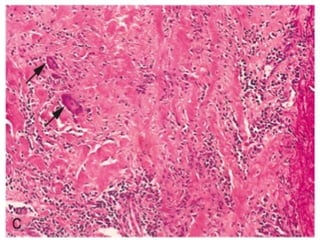

Morphology

 Segmental ,transmural ,necrotizing inflammation with

superimposed aneurysm and thrombosis

 2 stages

Acute Stage: Transmural inflammation of vessel with

polynuclear and mononuclear cells along with Fibrinoid

Necrosis.

Late Stage : Fibrous thickening of vessel wall

(nodular)extending into adventitia

Thrombus

Transmural inflammation of vessel